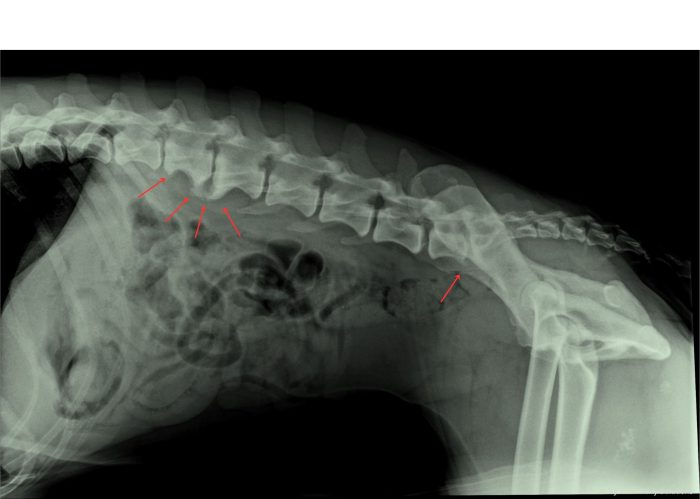

Artrose bij een hond

In de onderstaande foto’s is het verschilt te zien tussen een ruggenwervel van een hond zonder en met artrose. Hierbij is de artrose aangegeven met rode pijlen. Bij een röntgenfoto beoordeeld de arts of er aanwezigheid is van een versmalling van de gewrichtsspleet, wat duidt op een afname van het kraakbeen.